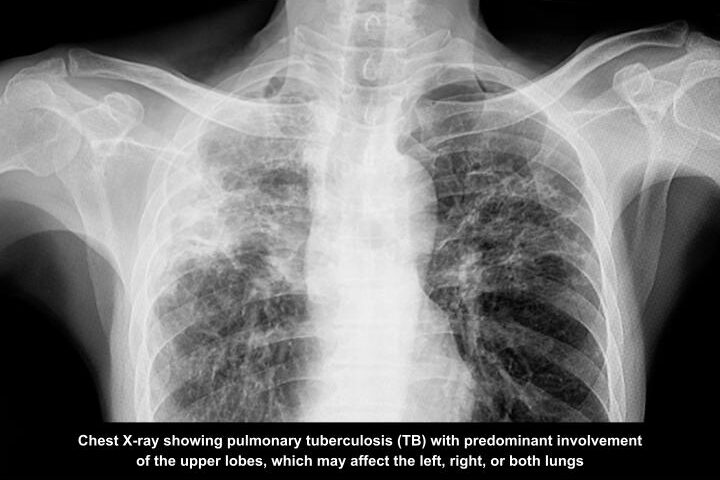

Melaka, 01 April 2026 – Tuberculosis (TB) may not spread as easily as influenza or COVID-19, but prolonged close contact in crowded and poorly ventilated spaces can still allow the disease to circulate quietly in communities.

The warning comes as Malaysia continues to see TB cases reported weekly. The Ministry of Health Malaysia reported 596 new TB cases nationwide up to Epidemiological Week 6 (EW 6/2026), bringing the year‑to‑date total to 3,161 cases. Sabah, Selangor and Sarawak recorded the highest numbers among all states.

According to the World Health Organization (WHO), Malaysia records about 122 TB cases per 100,000 people in 2023, with over 26,000 cases annually in recent years, highlighting its ongoing public health burden.

TB is less contagious than viral respiratory diseases, but prolonged exposure in dense indoor environments increases the risk of transmission. Dr Lo noted that households, workplaces, dormitories, prisons and crowded community events can facilitate transmission when someone with active TB is present.

The U.S. Centers for Disease Control and Prevention states that TB bacteria are transmitted via airborne particles, which linger longer in poorly ventilated areas, making prolonged exposure a key risk factor.